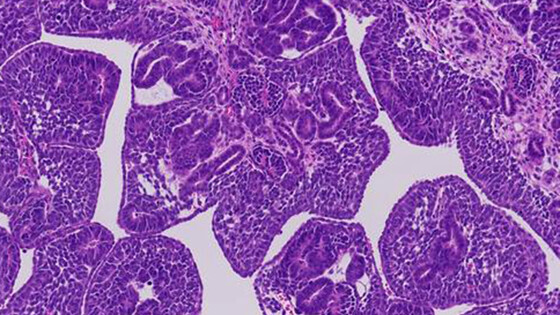

Одной из таких мутаций оказалась спонтанная поломка в гене FOXR2, происходящая еще в утробе. Она дает начало особому виду опухоли Вильмса с характерным внешним видом и «подписью» в РНК. В будущем это может помочь врачам быстрее распознавать такие случаи и подбирать целевые лекарства.